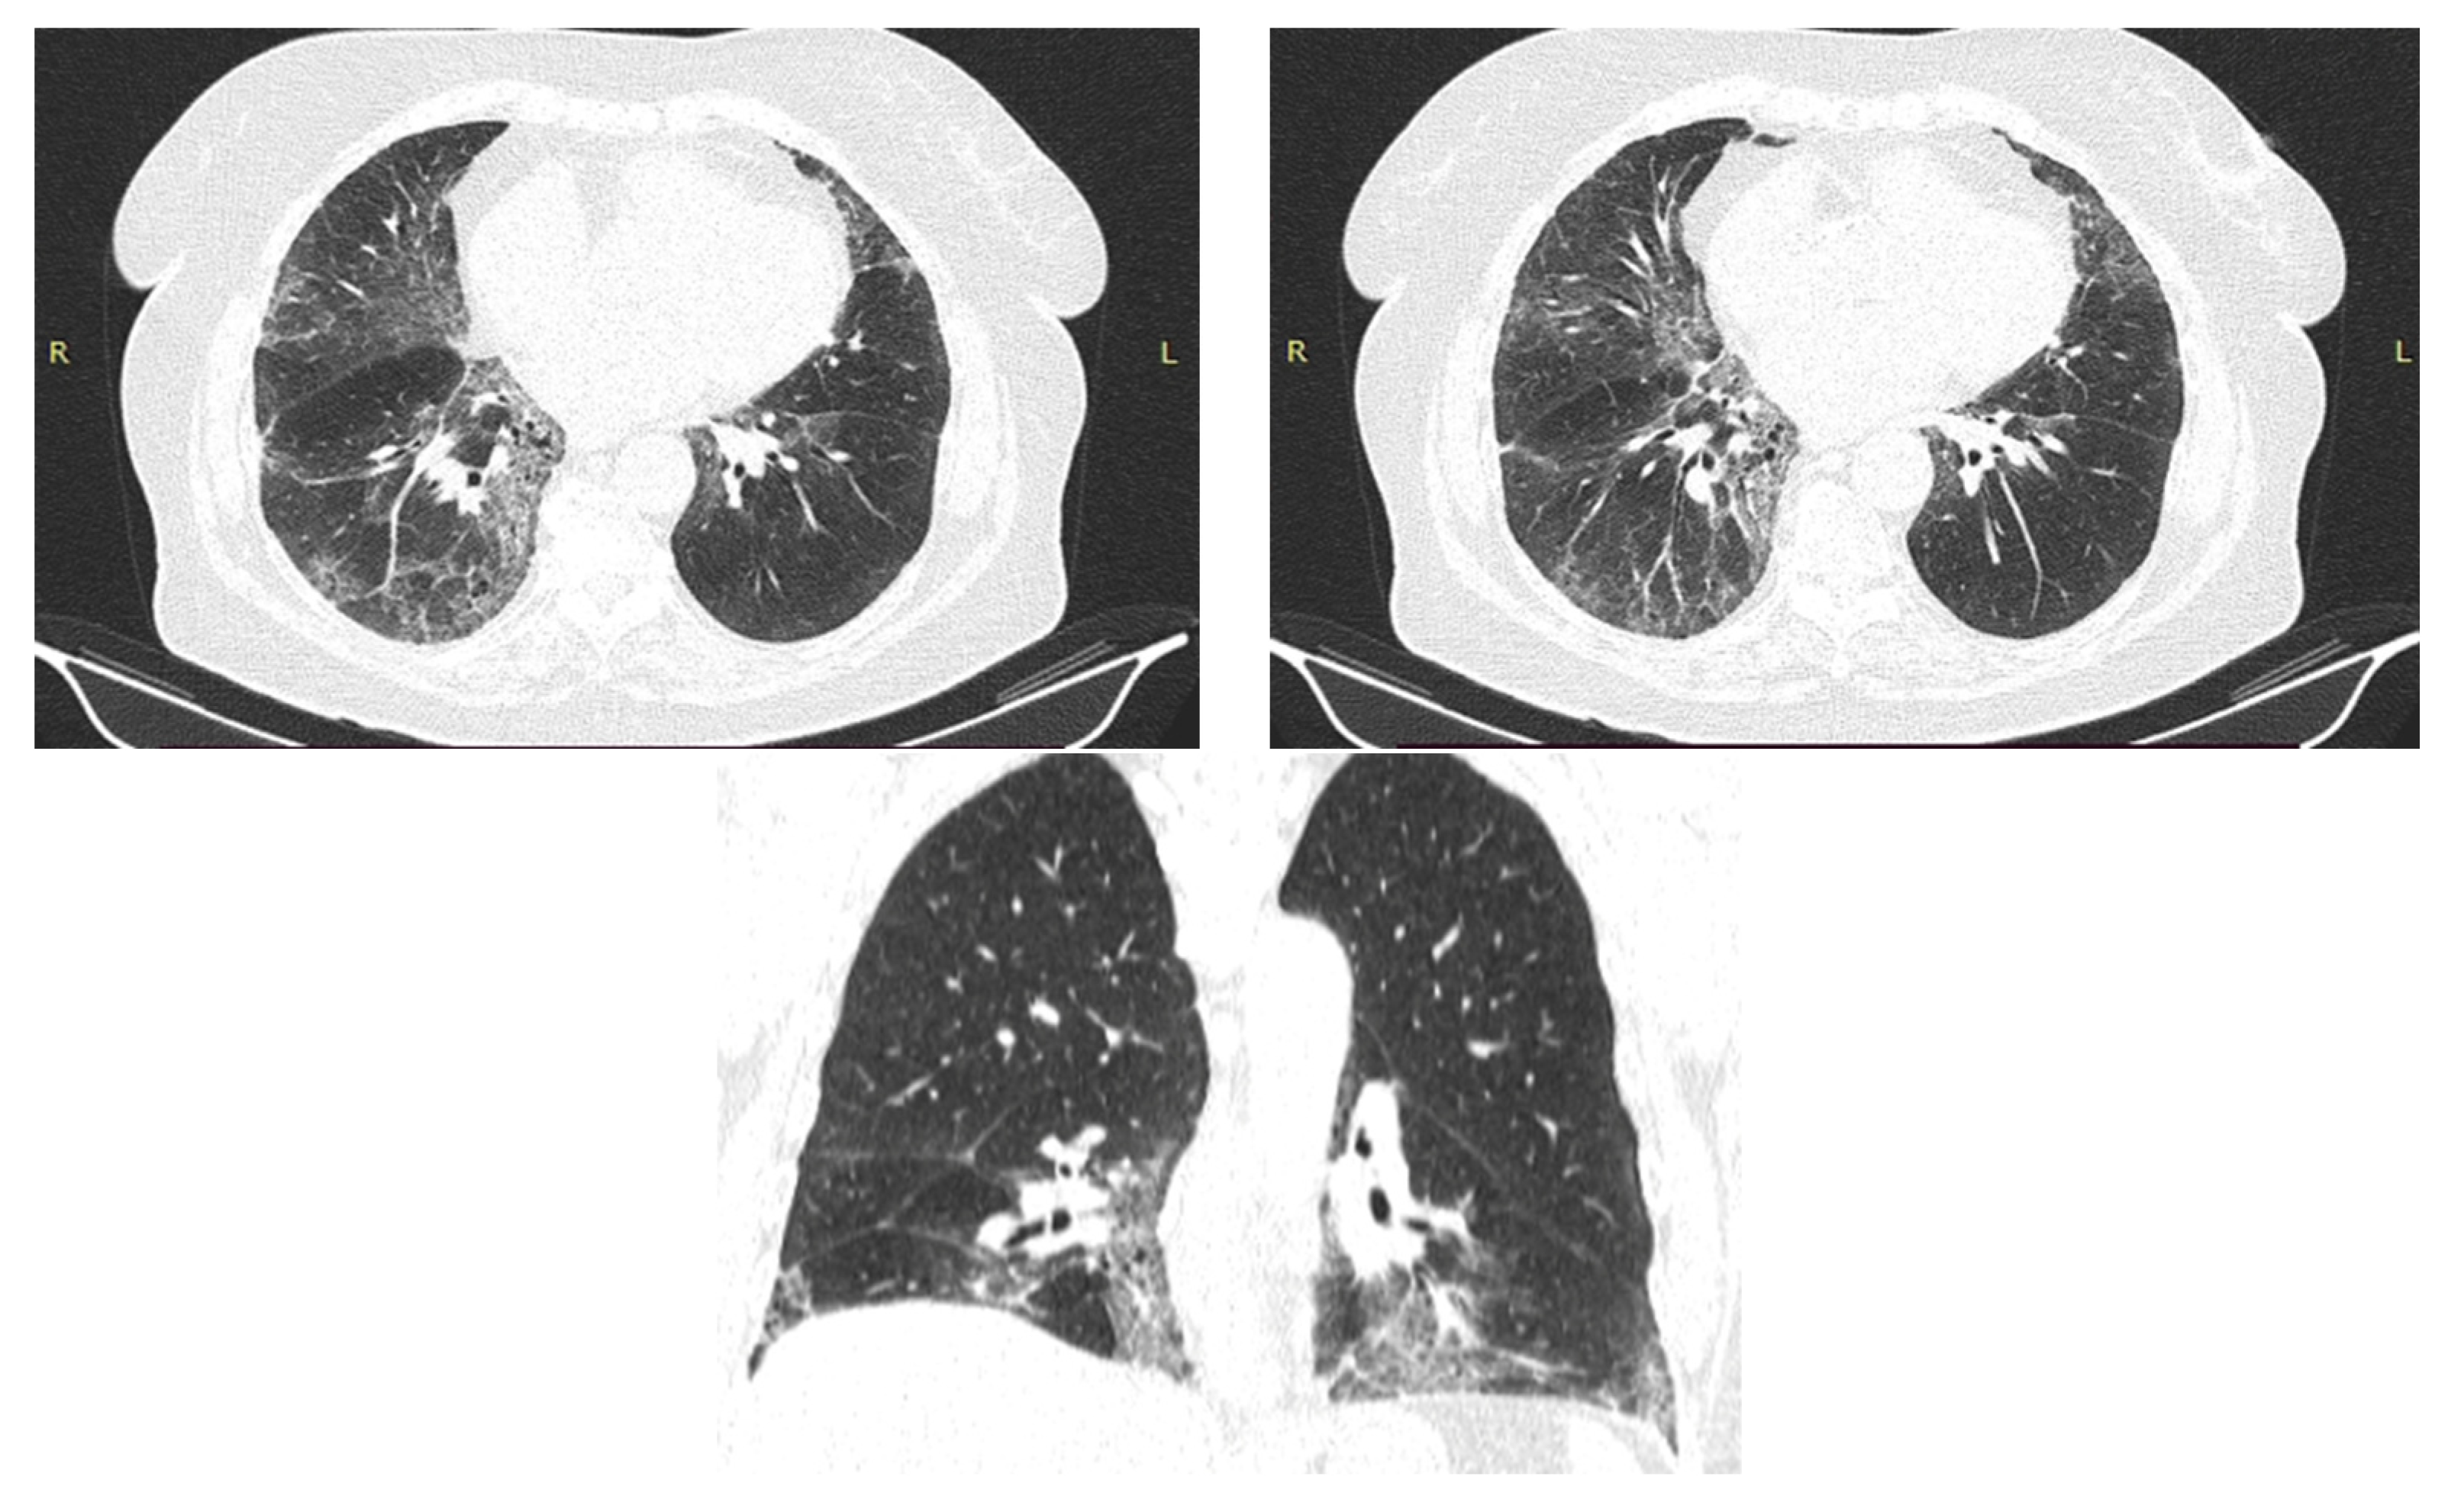

2.1. Case Presentation 1

2.2. Case Presentation 2

2.3. Case Presentation 3